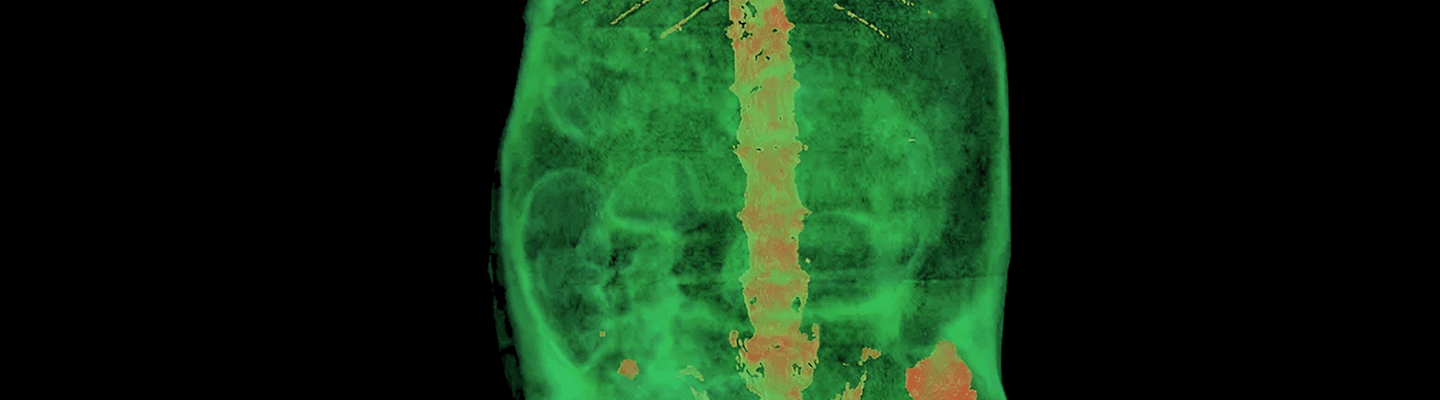

PET/RM 3T

Constituye el único equipo combinado de resonancia magnética y PET disponible a nivel nacional, integra un equipo PET basado en la tecnología de cristal continuo LYSO de alta sensibilidad con 2 anillos de 8 detectores que permiten obtener campos de visión de 80 mm (transaxial) x 148 mm axial, pudiendo llegar hasta 285 mm (axial) moviendo la cama, multiprocesadores de silicio compatibles con la RM, sensibilidad del 5 % y resolución lateral 9 % (norma NEMA) y resolución sub-milimétrica (< 0,7 mm) del equipo de RM de 3 Tesla y bobina de imán de 18 cm con tecnología Nyogen free, sin necesidad de llenado de quench, con una homogeneidad del imán de ±0.1 ppm (VS) [a 20 cm v, 20 ppm (DVS), 5.5 ppm (DSS)], necesaria para la obtención de una gran calidad de imágenes con gran resolución espacial y con un sistema de gradientes capaz de proporcionar 450 mT/m. El PET/RM presenta un sistema automático de posicionamiento del animal tanto en la modalidad PET como en RM y pantalla touch screen con cámara integrada para facilitar las labores de posicionamiento y seguimiento.

Constituye un sistema de tomografía de rayos X (fuente de 90 kV) con una resolución espacial 3D de menos de 10 μm y un sistema de gating respiratorio para sincronización prospectiva o retrospectiva de movimientos respiratorios durante la adquisición de la imagen. El sistema cuenta con una cámara refrigerada de rayos X de 12 bits, de 11 Mp con distorsión corregida (4000x2670) con acoplamiento de fibra óptica para centelleador. Capacidad de escaneo de cuerpo entero de rata y ratón: diámetro de escaneo 68 mm o 35 mm y longitudinal de hasta 200 mm por múltiples escáneres conectados de forma automática. Este equipo μCT es capaz de llevar a cabo ensayos longitudinales con una exposición de radiación inferior a 10 mGy además de co-registro de imágenes con el sistema PET o la RM.